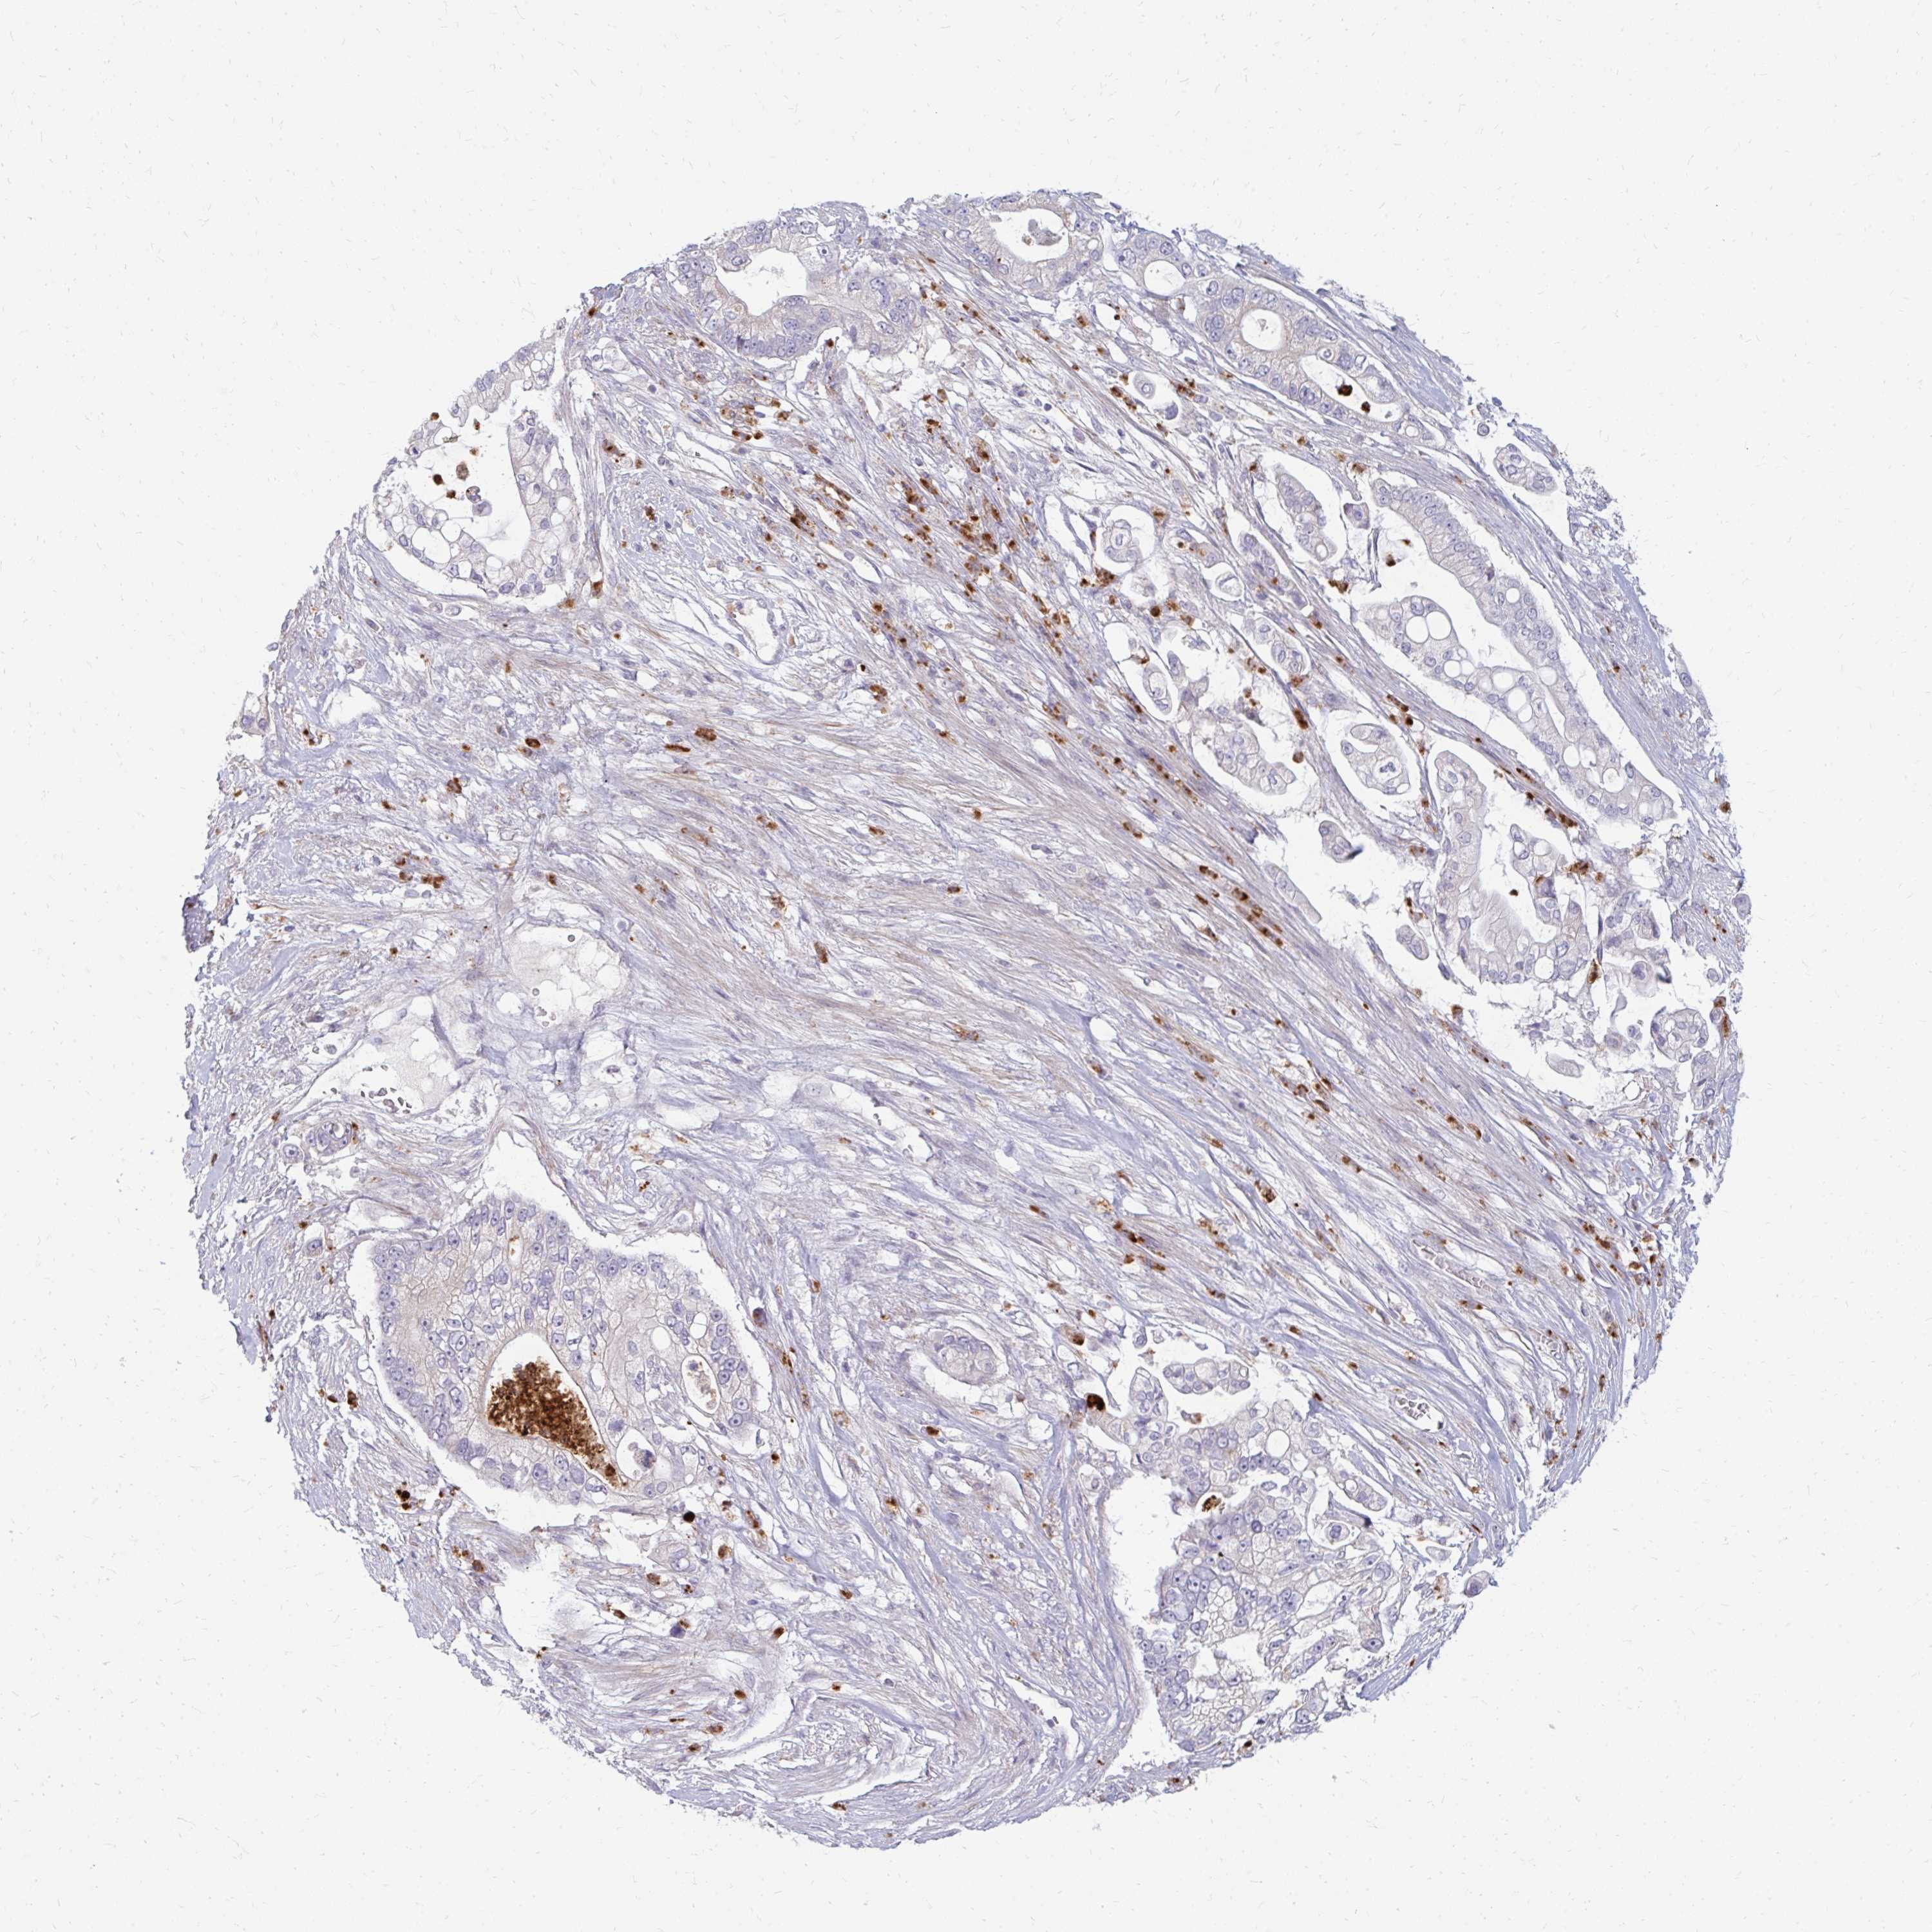

PANCREATIC CANCER - Protein expressioni

A mouse-over function shows sample information and annotation data. Click on an image to view it in a full screen mode. Samples can be filtered based on level of antibody staining by selecting one or several of the following categories: high, medium, low and not detected. The assay and annotation is described here.

Note that samples used for immunohistochemistry by the Human Protein Atlas do not correspond to samples in the TCGA dataset.

Antibody stainingi

Antibody staining in the annotated cell types in the current human tissue is reported as not detected, low, medium, or high, based on conventional immunohistochemistry profiling in selected tissues. This score is based on the combination of the staining intensity and fraction of stained cells.

Each image is clickable and will lead to virtual microscopy that enables deeper exploration of all samples and also displays staining intensity scores, fraction scores and subcellular localization as well as patient and tissue information for each sample.

Antibody HPA059737

Staining

High

Medium

Low

Not detected

Intensity

Strong

Moderate

Weak

Negative

Quantity

>75%

75%-25%

<25%

None

Location

Nuclear

Cytoplasmic/membranous

Cytoplasmic/membranous,nuclear

Adenocarcinoma, NOS